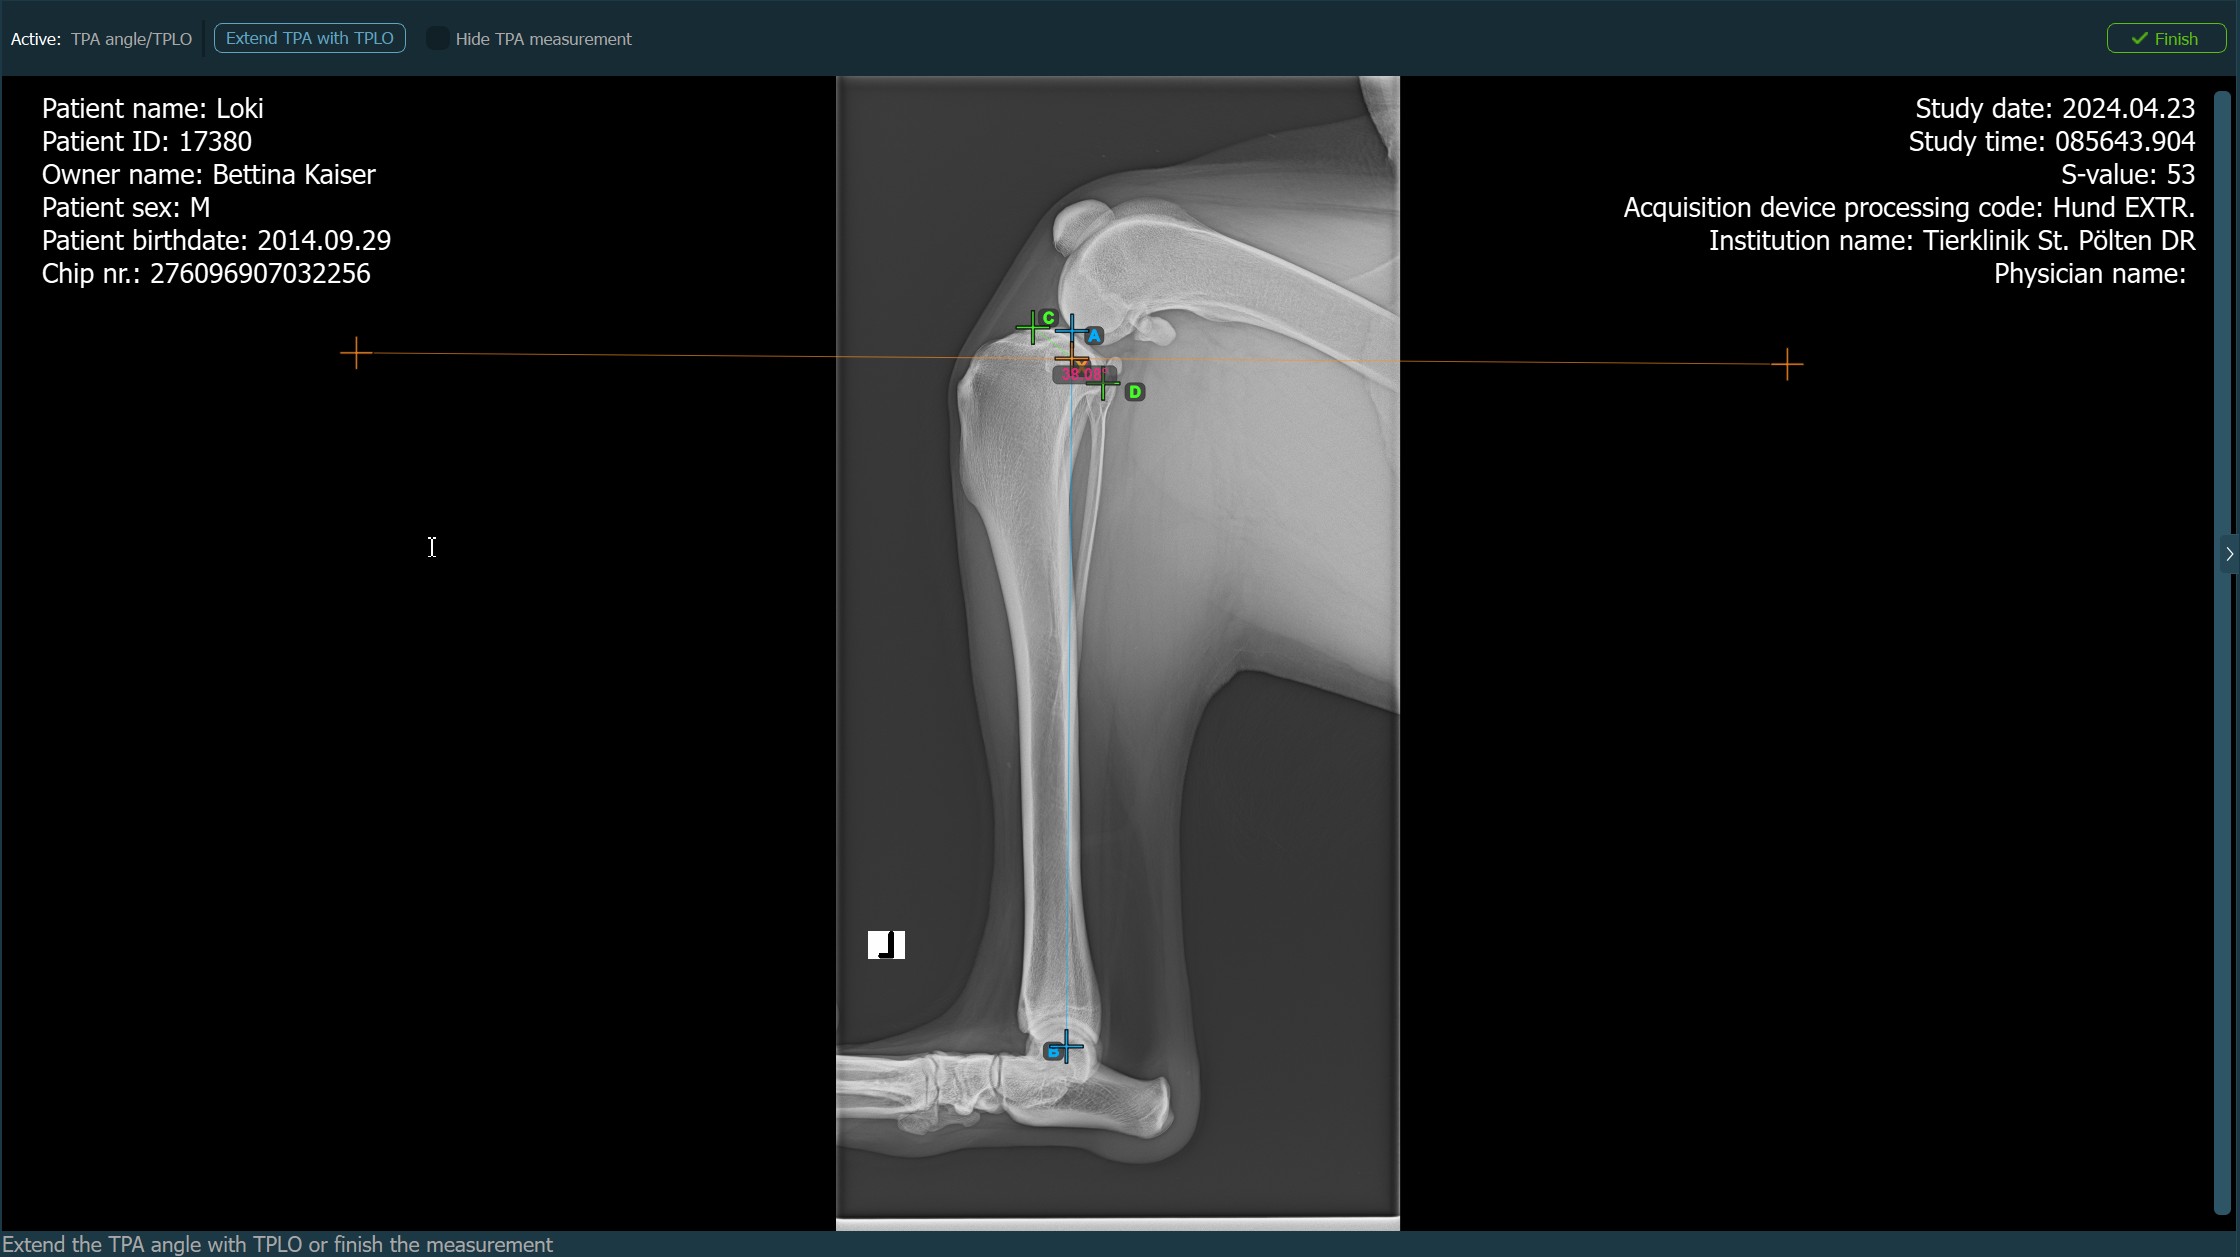

When the TPLO extension to the TPA Angle measurement is enabled, choose one of the available options from the advanced measurement mode toolbar to continue/complete the measurement. The TPA Angle measurement is automatically completed otherwise.

Press

Finishto confirm and complete the TPA Angle measurement without the TPLO extension.Activate the TPLO extension by using the

Extend TPA with TPLObutton.Hide/Show the TPA Angle measurement during the TPLO extension by toggling the

Hide TPA measurementcheckbox.

Before completing the TPLO extension, users can modify the parameters of the measurement required to calculate the rotation distance for the procedure in the advanced measurement mode toolbar.

Fix the TPA Angle calculation by toggling the

Fixcheckbox. Any modification to the TPA Angle will otherwise be reflected in the rotation distance calculation.Enter the desired TPA Angle of the TPLO procedure in the

Desired TPA (°)input field.To recalculate the sawblade size, enter the desired value in the

Sawblade Sizeinput field.

Press Calculate rotation distance to perform the required calculations for the TPLO procedure. The calculated rotation distance will be shown in the advanced measurement mode toolbar.

The TPA Angle measurement with the TPLO extension will be active until the user presses the Finish button in the right corner of the advanced measurement mode toolbar.

Modify the position of the points to recalculate the TPA Angle measurement. To recalculate the rotation distance for the TPLO procedure, double-click on the surface of the entire measurement and open the advanced measurement mode toolbar to modify the required parameters.